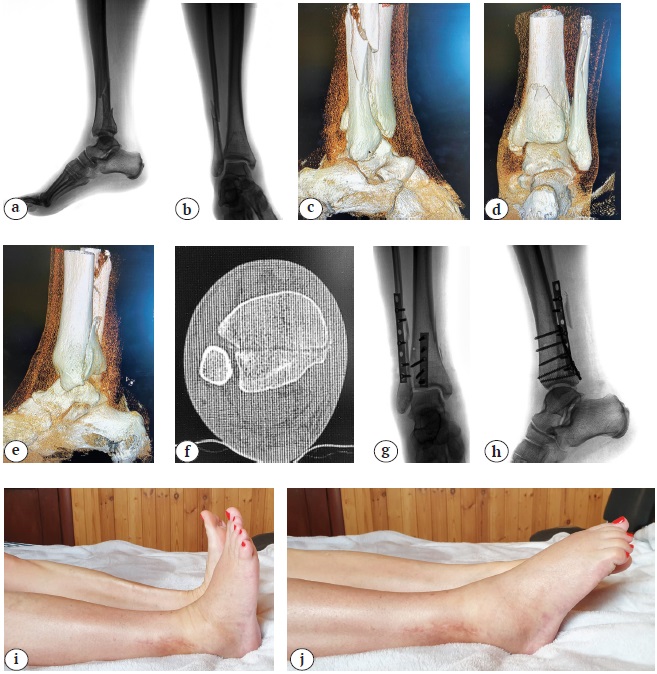

Пример использования методики представлен на рисунке 3.

Рис. 3. Хирургическое лечение пациентки с переломом типа 44С2.3:

а, b — первичные рентгенограммы в прямой и боковой проекциях;

c, d, e, f — данные КТ, показывающие размер заднего края ББК;

g, h — послеоперационные рентгенограммы в прямой и боковой проекциях — анатомичная репозиция костных отломков в области голеностопного сустава;

i, j — функциональный результат лечения через 48 нед. после травмы

Fig. 3. Surgical treatment of a patient with a fracture 44C2.3:

a, b — primary X-rays in AP and lateral projections;

c, d, e, f — CT data showing the size of the posterior edge of the tibia;

g, h — postoperative X-rays in AP and lateral projections — anatomical reposition of bone fragments in the ankle joint;

i, j — functional result of treatment 48 weeks after injury